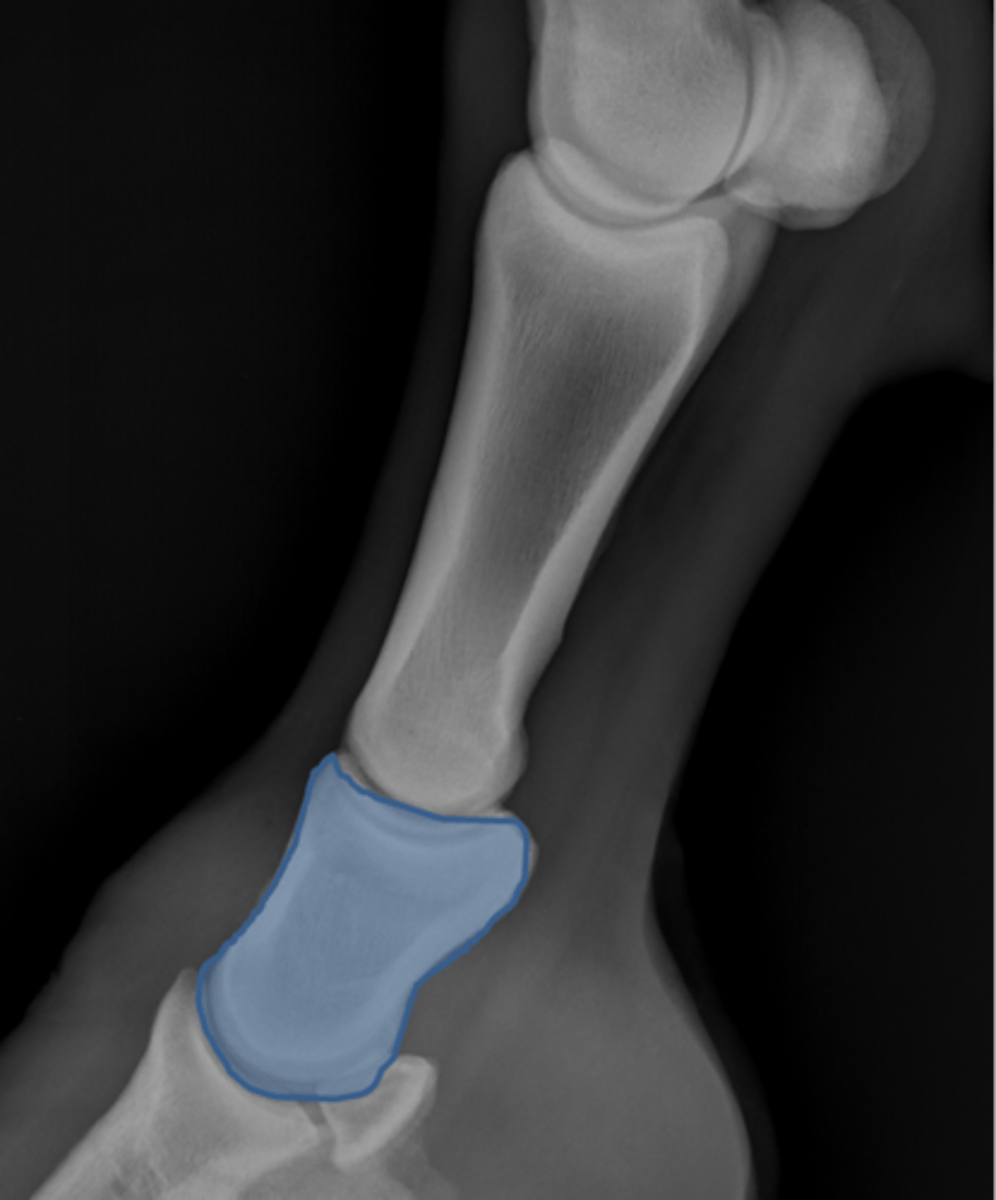

Short pastern (P2)

Long pastern (P1)

Pastern joint (proximal interphalangeal joint)

Distal sesamoidean ligament

Long pastern (P1)

Short pastern (P2)

Medullary cavity

Nutrient foramen of P2

Extensor process of P3

Fetlock joint, LM

ID joint and view

Fetlock joint, DP

ID joint and view